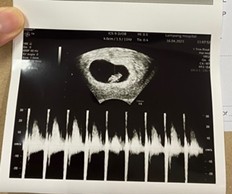

กี่ weeks ถึงจะตรวจเจอการเต้นของหัวใจลูกน้อยคะ

ตอนนี้น้อง 6 weeks 2 days

เราเจอตอน7w2d